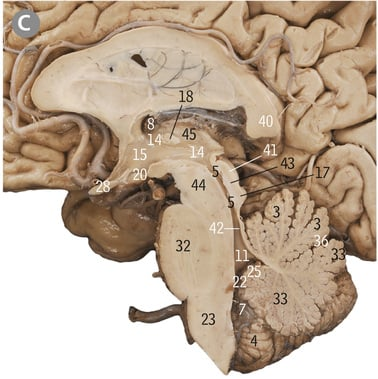

24

Midbrain

32

Pons

23

Medulla oblongata

5

Cerebellum

17

Inferior colliculus

41

Superior colliculus

Cerebral aqueduct

43

Tectum of midbrain

44

Tegmentum of midbrain

Gracile tubercle

1

Cuneate tubercle

4

4th/fourth ventricle

Floor of fourth ventricle

Middle cerebellar peduncle